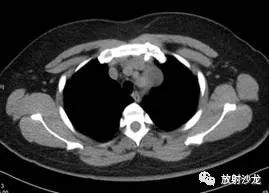

CT平扫

在影像上,典型的神经鞘瘤一般位于脊柱旁,圆形或卵圆形,边缘光滑锐利,与周围结构分界清晰,密度一般欠均匀,较大者易囊变,实性部分呈软组织密度,CT值近似于肌肉,有完整包膜,少数可含脂类物质、钙化。若肿瘤呈哑铃状生长于椎管内外,椎间孔可扩大,实性部分增强动脉期强化,静脉期及延迟期强化进一步持续并略增强,肿块以中等程度强化者居多,囊性部分无强化。MRI检查中,神经鞘瘤在T1WI上一般呈等至低信号,T2WI上呈不均匀高信号,特别是囊变区可呈高信号,较大者可在T2*WI上见含铁血黄素沉积。

综上,神经鞘瘤一般见于后纵隔,前纵隔发生者较少,但在影像学检查上具有一定的特点。本例患者的前纵隔占位分界明显,且呈钻缝样生长,在CT上可见低密度区,增强扫描表现不均匀强化,符合神经鞘瘤的表现。